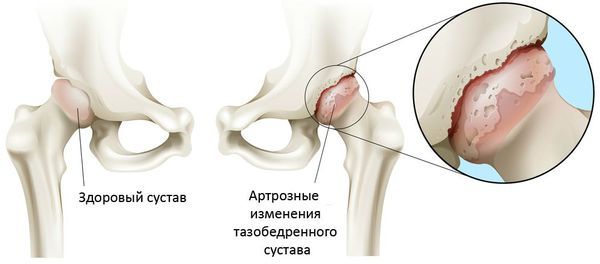

Такие повреждения могут сопровождаться смещением мышц, мягких тканей, сухожилий или костно-хрящевых фрагментов, которые в результате остаются между бедренной головкой и вертлужной впадиной. Это приводит к невправимости вывиха или быстрому изнашиванию хряща и развитию коксартроза.

Коксартроз

Повреждение сосудов и губчатой костной ткани приводит к снижению кровоснабжения и отмиранию (некрозу) головки бедренной кости. Некроз начинает проявлять себя в течение 1–2 лет после травмы, он сопровождается постепенно нарастающей болью и прогрессирующим ограничением движений в тазобедренном суставе. Если вправить вывих в течение первых 6 часов после травмы, вероятность формирования такого некроза составляет 30 %, в противоположном случае риск развития этого осложнения резко возрастает [6][10][18]. Чтобы вовремя остановить развитие некроза, нужно регулярно наблюдаться у врача даже после вправления вывиха.

Нарушение кровоснабжения также может возникнуть при сочетании вывиха и перелома впадины, если на опорной поверхности впадины образуются ступенеобразные выступы смещённых фрагментов, которые травмируют головку бедра. Помимо некроза, такое состояние также может привести к формированию посттравматического коксартроза.